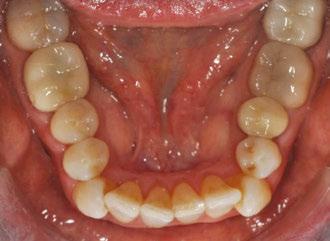

Case 2: Deep bite, mild crowding, ectopic cuspid, posterior crossbite

The patient was a 27-year-old male whose main concerns were crowding and poor smile esthetics. The clinical exam also revealed he had a maxillary left second bicuspid in lingual crossbite, a deep overbite due to an excessive Curve of Spee, and an ectopic/under-erupted maxillary left cuspid.

Like the previous case, we started the patient’s treatment with simultaneous premolar expansion, second molar constriction, and proclination of incisors, followed by retrusion and retraction of lower incisors to the final position. One additional challenge was the UL5 crossbite; however, this was treated out quite predictably, with some compensatory buccal root torque

during expansion. This was greatly aided by the distal anchorage of the UL6 and UL7, which made this a predictable movement. The real challenge in this case was the ectopic UL3. My initial setup failed to stage this tooth’s extrusion properly and relied too heavily on a gingivally beveled attachment for anchorage.

The attachment was rotated at 45 degrees from the occlusal plane to attempt simultaneous mesial in rotation and extrusion; however, only the former movement was successful. During my second refinement, 29 weeks after initial delivery, I programmed visible space mesial and distal to this tooth, then staged it to procline with buccal movement while maintaining its current vertical position. This was followed by simultaneous retraction, retroclination, and extrusion, which proved far more successful but didn’t get me to my final position. In this case, a third refinement was necessary, repeating the same protocol and obtaining an excellent outcome. The total time in treatment was 21 months.

Figure 9: Case 2 initial photos

Figure 10: Case 2 final photos